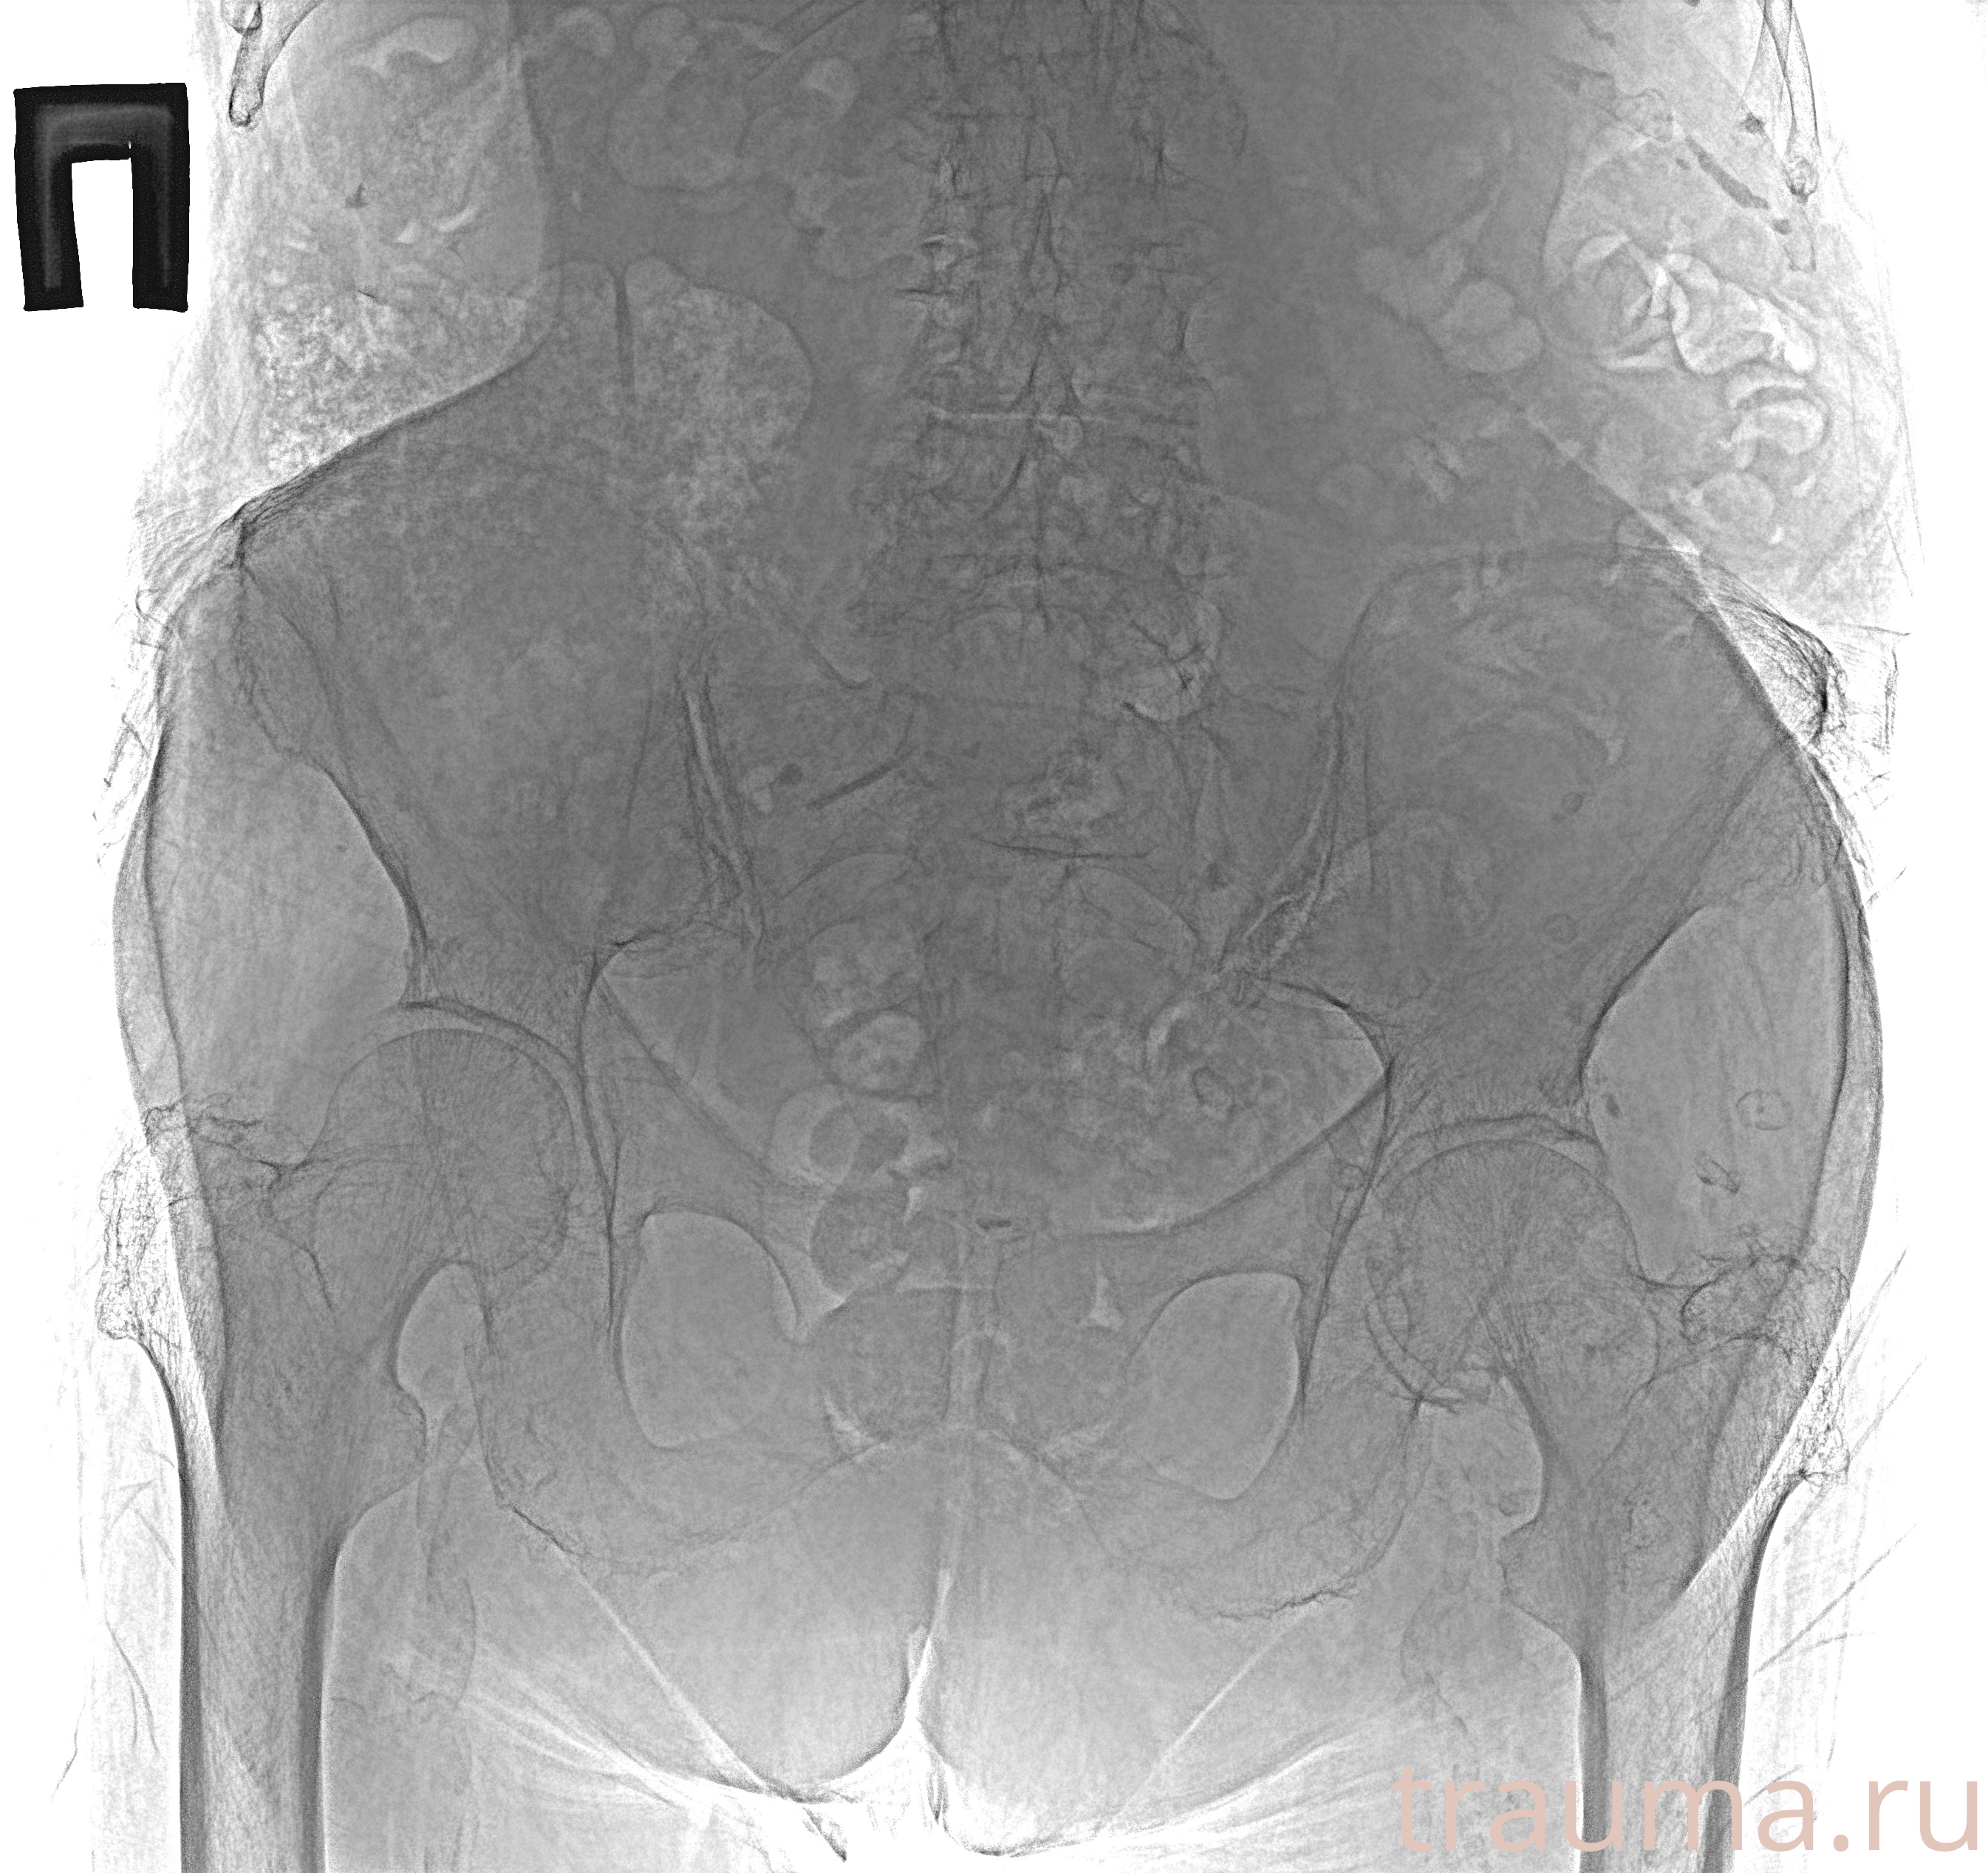

Рентген на дому: по вашему адресу приезжает врач-рентгенолог, травматолог-ортопед с мобильным рентгеновским аппаратом, проводит диагностику травмы или заболевания, делает необходимые рентгенограммы, дает рекомендации по дальнейшему лечению. Получить качественные снимки в домашних условиях возможно благодаря уникальной методике, разработанной МосРентген Центром для института  Склифосовского

Яркость: 1   Контраст: 1   Инвертировать: 0 Увеличение: 1

Перетаскивайте мышь вверх/вниз для контраста, влево/право для яркости. Прокрутка колесом изменяет масштаб. Нажмите Сбросить для возврата к исходному изображению. При увеличении держите мышь в той области, которую хотите рассмотреть.